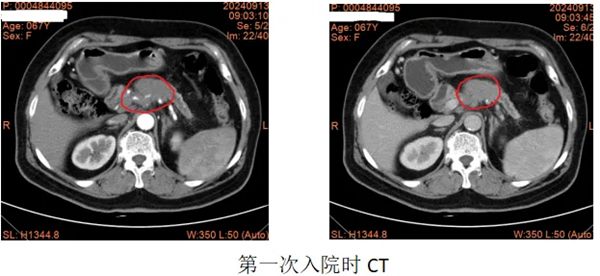

该患者来自河北省,6个月前因左上腹部疼痛进行MRI检查提示:胰颈部占位,考虑胰腺癌可能性大,同层面脾动脉、脾静脉及腹腔干受侵可能性大。经过2个月艰辛的求医之路,疗效甚微。2024年9月,慕名来到郑大五附院李晓勇教授门诊,经过李教授的认真阅片及详细查体,考虑局部进展期胰腺癌,入院后请肿瘤内科、消化内科、影像科、临床营养科等相关科室行MDT讨论,共同制定治疗方案:按“AG d1,8天 q21天”方案化疗,化疗后若肿瘤缩小,行纳米刀消融术。经过“AG”方案4疗程的化疗,影像学检查提示肿瘤明显缩小,Ca19-9降至正常。经过李晓勇教授、陈艳军主任医师带领科室再次详细回顾患者病史、查体及治疗经过,一致同意为患者进行胰腺肿瘤纳米刀消融术。